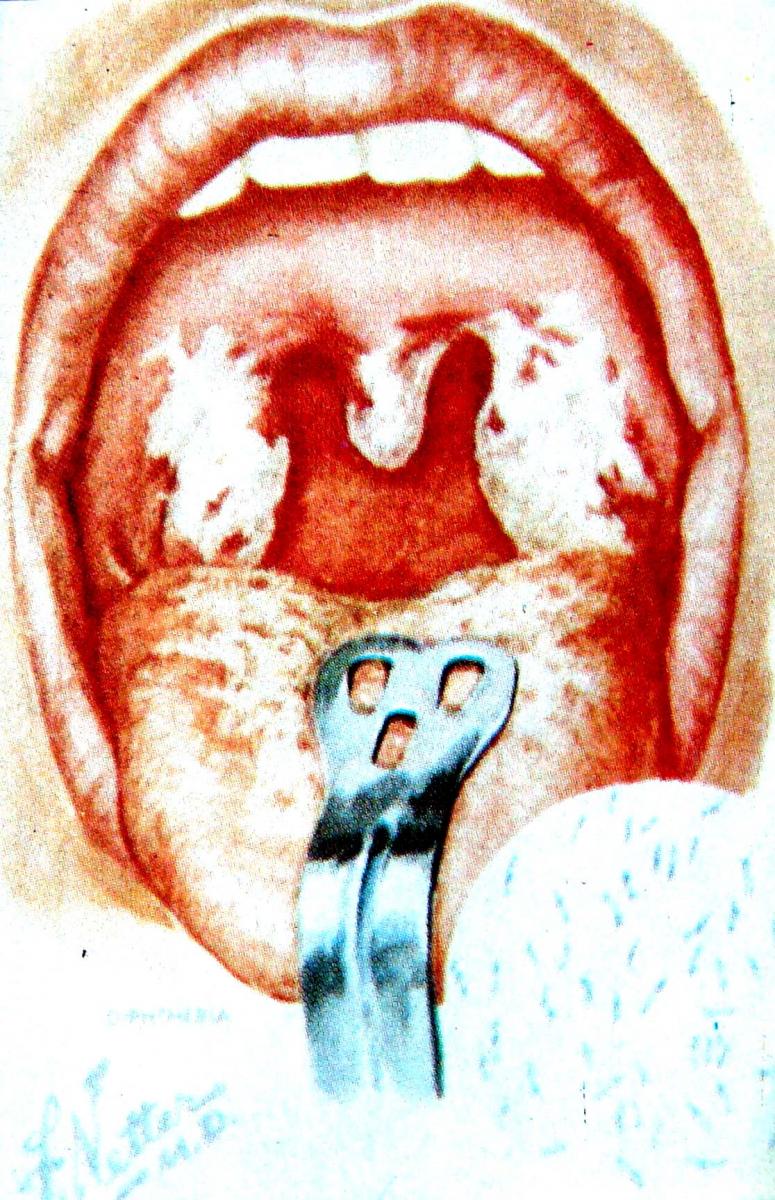

5. เด็กที่เป็นคอตีบ (ซึ่งมักมีอาการหอบร่วมกับไข้ เจ็บคอ อาเจียน) จะพบว่า ต่อมทอนซิลโตแดงและมีฝ้าหนองติดเป็นแผ่นบนต่อมทอนซิล และผนังลำคอ เขี่ยออกยาก ถ้าใช้แรงเขี่ยจะทำให้เลือดออก (รูปที่ 4)